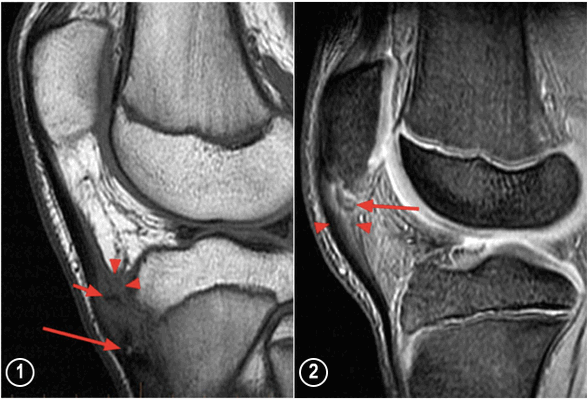

МРТ коленных суставов (сагиттальная проекция): 1 - снимок коленного сустава при болезни Осгуда-Шлаттера (длинная стрелка показывает отделившийся костный фрагмент бугристости большеберцовой кости, короткая стрелка - костный фрагмент выше бугристости большеберцовой кости, наконечники стрелок - увеличение поднадколенниковой глубокой синовиальной сумки; 2 - снимок коленного сустава при болезни Синдинга-Ларсена-Йоханссона (длинная стрелка показывает костный фрагмент на нижнем полюсе надколенника, наконечники стрелок - утолщенную и отечную проксимальную часть связки надколенника).